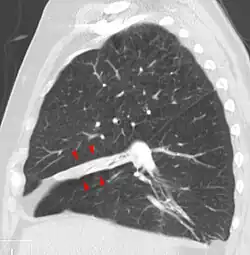

Vista sagital de lóbulo médio colapsado.

O colapso pode ser detectado por[2]: